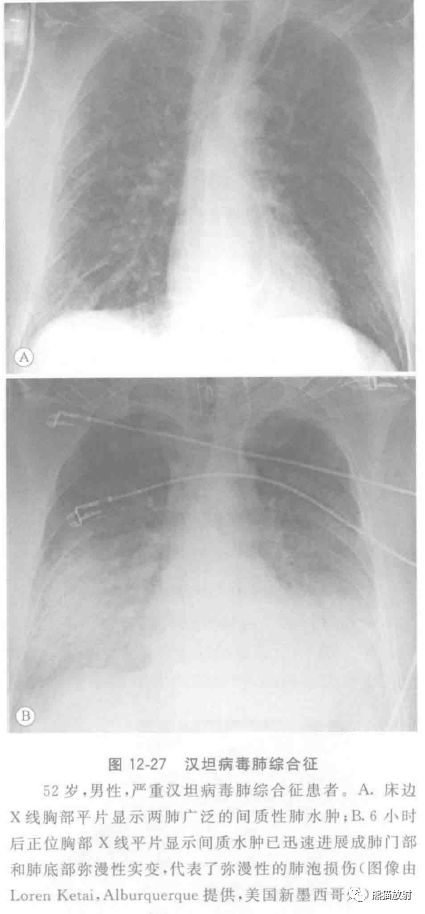

1993年春天,在美国西南部的健康成年人中出现一种啮齿动物源性人畜共患疾病,其特点是严重的急性呼吸衰竭,临床进展迅速及高病死率。

汉坦病毒感染引起的弥漫性气腔病变,称为汉坦病毒肺综合征(HPS)。接受治疗的患者死亡率达35%。组织学上特征性改变为弥漫性肺泡损伤,分为渗出期和增殖期。

影像表现初期可以正常,但逐步恶化,呈现肺水肿和急性呼吸窘迫综合征的征象(图12-27)。胸部X线平片表现反映HPS和急性呼吸窘迫综合征(ARDS)肺泡上皮损伤的程度。